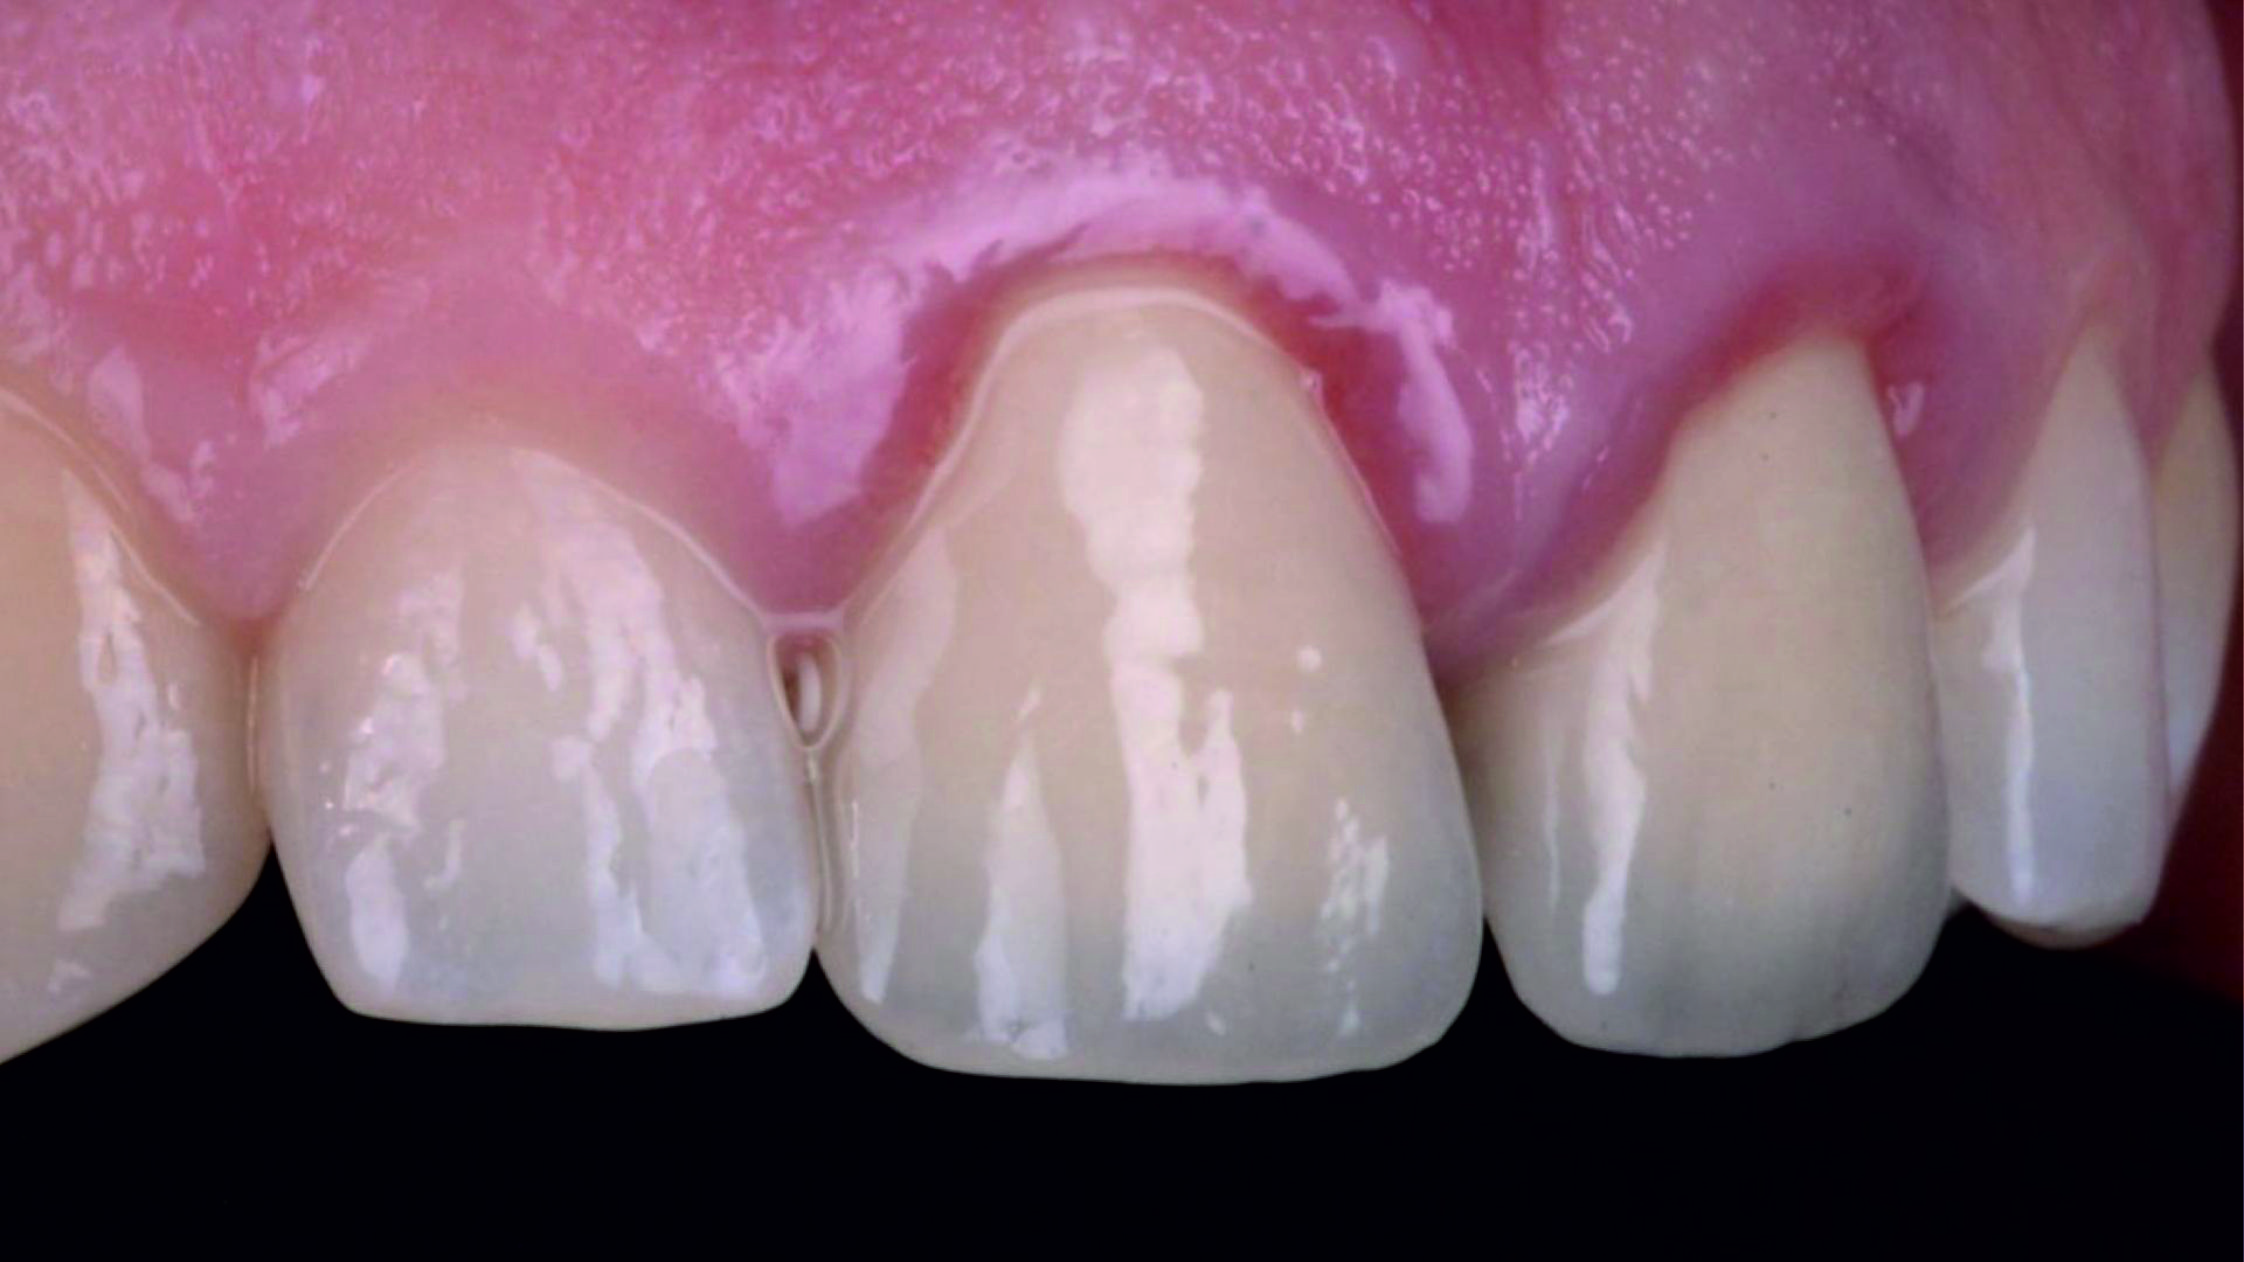

Фото 1. Початкова ситуація: жінка віком приблизно 35 років, із двома металокерамічними коронками, встановленими на верхніх центральних різцях.

Основні скарги: асиметрія центральних різців, запалення й кровоточивість ясен навколо коронок, загальне невдоволення естетикою цієї зони.